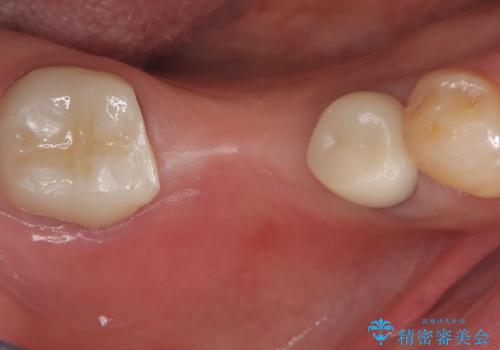

セラミックインレーを除去したところ、残存歯質が少なく破折のリスクを説明し、オールセラミッククラウン(スタンダード)でのやり替えとなりました。

オールセラミッククラウンの膨隆で下部鼓形空隙を適切な大きさに調整しました。